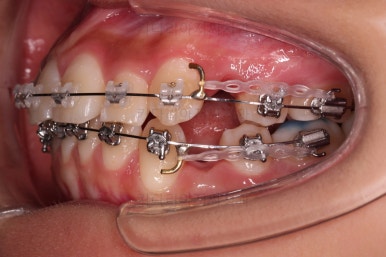

적절한 위치의 치아를 발치하고요.

이 뽑은 공간을 닫아주며 앞니를 뒤로 넣어줘요.

반복적으로 당겨주며 교합, 중앙선, 기울기, 입매 등을 맞춰 나갑니다.

치료 종료시의 모습이에요.

총 21개월 걸렸고요.

발치를 중간에 결정했기 때문에 조금 지체된 면이 없지 않았으나 기간부터 치료 결과까지 만족스러운 치료였습니다.

치여링 가지런해졌고, 교합과 중앙선 등 입안의 모습이 매우 좋아졌어요.

불규칙하게 마모되어 있던 치아의 개별 형태도 약간씩 다듬어 드렸고요.

입매도 본인이 원하는 정도로 만들었고, 웃는 모습, 뻐드러졌던 각도도 매우 잘 개선이 되었네요.

기울어보이던 치열의 경사도 개선이 되었고요.

전반적으로 만족스러운 치료였습니다.